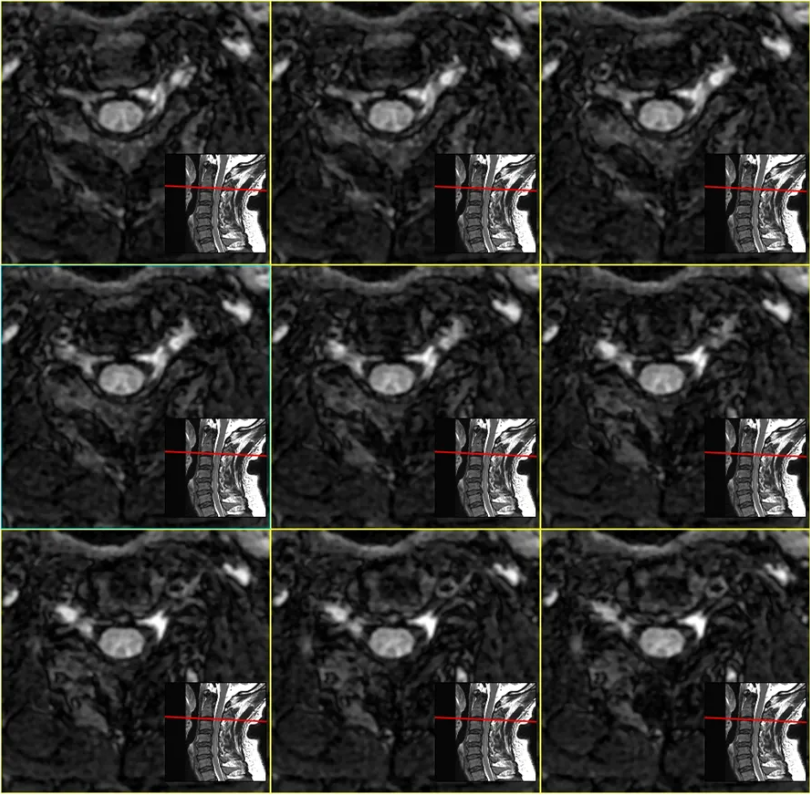

伪影吧。参数有问题。机器好久没有停机保养了。 放病人下来? 赶紧弄下一个, 晚饭约了心仪许久的妹子(帅哥)。。。 三、放患者走,还是继续扫描? 这是一个哲学问题! Ax CUBE T2FLAIR来一个吧。妹子(帅哥)应该不会因为晚到4分钟生气吧。。

重建效果图: